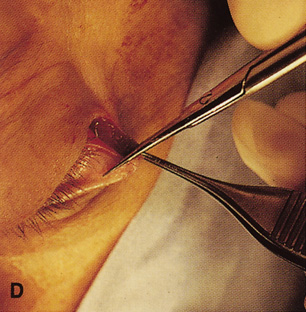

wall still can be carried out. | Fig. 9. A,B. Coronal and axial CT images of a large intraconal neoplasm. C. Because it was felt to represent a well-encapsulated cavernous hemangioma, this

lesion was a candidate for removal via an eyelid crease orbitotomy

without bone removal. The eyelid crease incision marked. D. Incision made with scalpel. E. Orbicularis muscle is tented up and incised to expose the underlying septum. F. Dissection of a skin-muscle flap deep to orbicularis exposes the orbital

septum and superior orbital bony rim. G. Cutting cautery is used to incise periosteum along the superior and lateral

rims; finger palpation of the bone helps to direct this incision. H. Periorbita is elevated along the mesial surface of the lateral orbital

rim in order to expose the deep orbital tissues. I. The cavernous hemangioma is visualized in the wound. Retraction is provided

by one or more malleable retractors. J. Cryoprobe is affixed to the hemangioma to facilitate manipulation of the

lesion. K. Large cavernous hemangioma after removal through the eyelid crease incision

which was accomplished without bone removal. L. Periorbita is reattached over the lateral rim. M. The eyelid crease incision is closed with a running suture. |